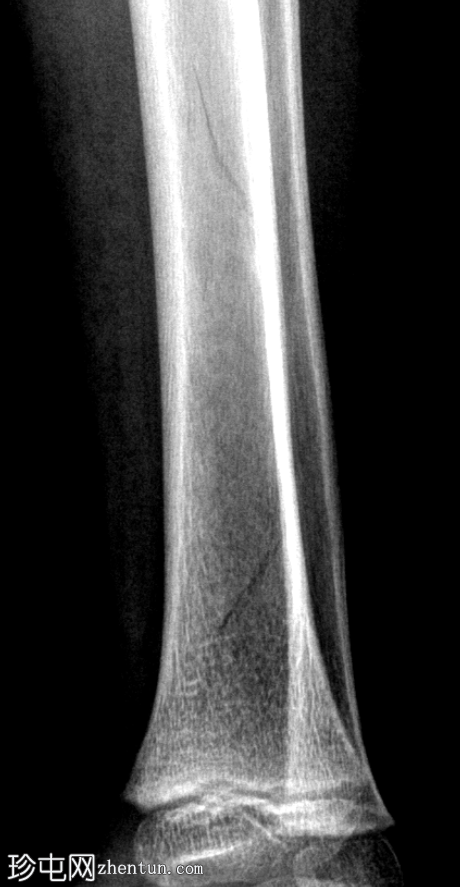

正位

侧位

胫骨远端骨干可见一条螺旋状透亮线,提示骨折(正位、侧位)。

应用锐化算法并放大正位片(骨折由近端向远端)和侧位片。

幼儿骨折是指幼儿因扭转(足部着地时股骨内旋)导致的胫骨中远端轻微移位的螺旋状骨折,这种情况可能发生在儿童绊倒时。患者接受了6周的石膏外固定治疗。

请注意,应用锐化骨算法并放大图像后,骨折及其范围会更加清晰可见。